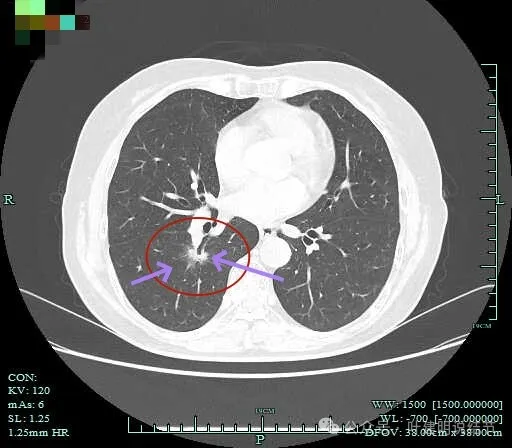

实性成分较多,边缘毛刺。

毛刺征明显,而且是短毛刺且锐利。

毛刺。

边缘区也不光滑,显毛糙。

靶重建显示混合密度,边缘毛糙,内部杂乱,灶内支气管通气且僵硬。